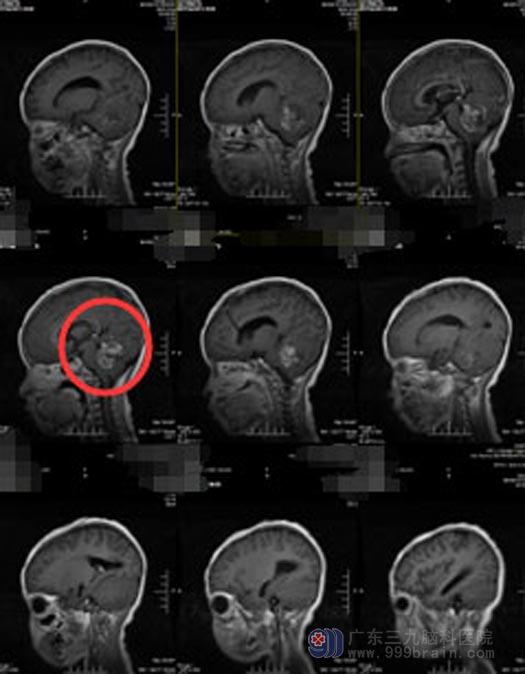

当地医院就诊,脑部CT检查提示“四脑室占位性病变、梗阻性脑积水”,医生建议转上级医院。在广东三九脑科医院综合神经外科,急诊行“脑室外引流术”缓解脑高压症状,化疗后实施“四脑室占位病变切除术”,肿瘤顺利切除。手术后,小泽还需要进入下一阶段的康复。

手术前